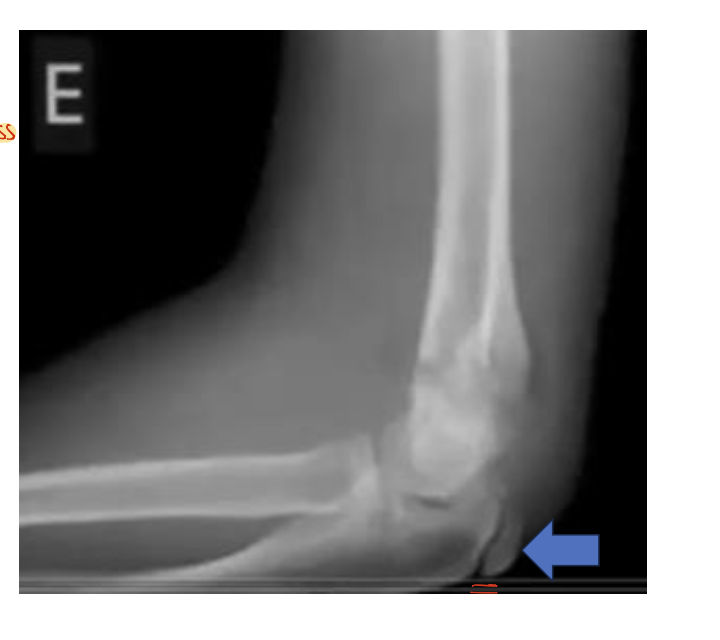

Identify the structures ? view?

Elbow Joint, Lateral View